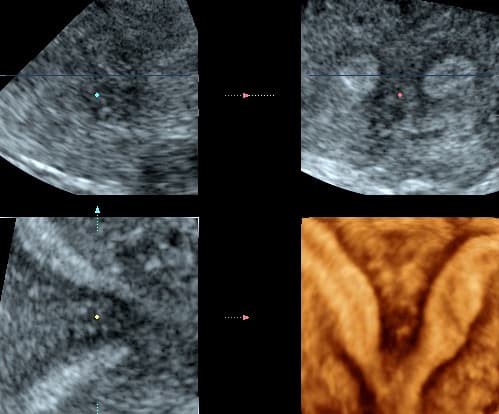

Ultrazvučna procjena maternične šupljine danas je najjednostavniji i najpristupačniji oblik postavljanja sumnje i često dijagnoze razvojnih anomalija. Konačna dijagnoza uz planiranje korekcije u žena koje žele ostvariti trudnoću postavlja se histeroskopskim i laparoskopskim putem kada se procjenjuje i opsežnost anomalije odnosno prisutnost i prohodnost jajovoda.

Transvaginalnim ultrazvukom je osjetljivost u dijagnostici septiranog uterusa 100%, a specifičnost 80%. Transvaginalnim ultrazvukom može se precizno odrediti indentacija (uleknuće) u fundusu i na taj način točno razvrstati radi li se o septumu koji treba operirati (aplaniran fundus) ili dvorogoj maternici, koju ne treba operirati (konveksan fundus).

Diferencijalnu dijagnostiku osobito pospješuje primjena trodimenzionalnog i kontrastnog ultrazvuka, kada se u materište instilira fiziološka otopina ili kontrast koja se potom pregledava u svim dimenzijama. Kontrastni ultrazvuk ne samo da je koristan u evaluaciji kongenitalnih anomalija uterusa, već omogućuje i ispitivanje prohodnosti jajovoda. Za trodimenzionalni ultrazvuk se kaže da nalazi uterusa koreliraju s vanjskom konfiguracijom uterusa nađenom pri laparoskopiji, da mu je osjetljivost i specifičnost 100% za dijagnozu velikih anomalija Müllerovih cijevi, i 100% preciznost za bikornualni uterus.